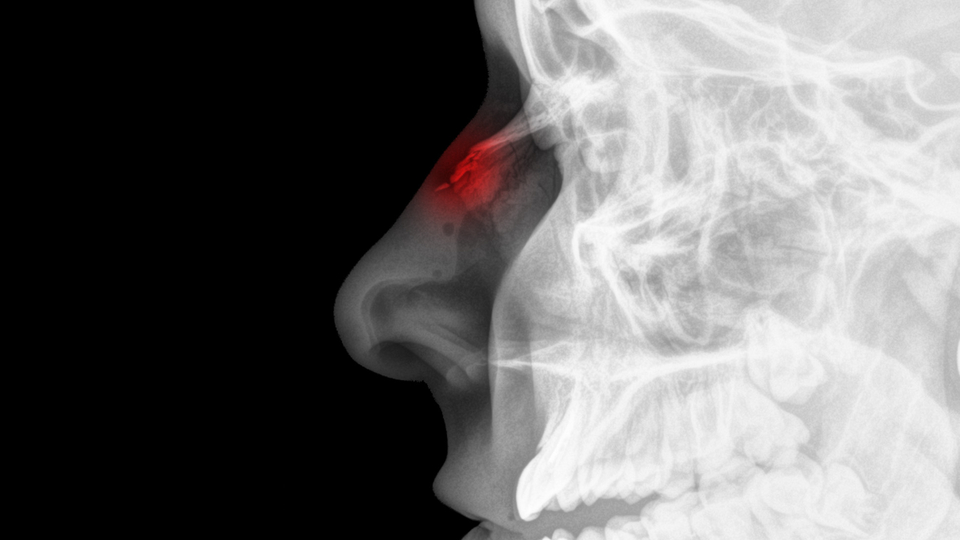

Haberler Sağlık Burun kemiği kırıkları tam olarak ne zaman iyileşir? | Sağlık Haberleri

Burun kırıkları genellikle darp veya trafik kazası gibi travmalar sonucunda oluşurlar. Bir burun kırığı ilk oluştuğu anda, burnun dış kısmındaki, burnun dışındaki piramidi oluşturan kemikler yerinden oynayabilir veya ilk anlarda ödemin etkisiyle kırığın şiddeti tam anlaşılamayabilir. Genellikle bu tarz vakalarda mutlaka bunun dışında bir şişlik veya yara ödem gözükmese bile mutlaka burnun iç kısmının detaylı muayenesi yapılır. Çünkü burnu kıracak kadar şiddetli bir darbe, burnun iç kısmında da duvarı kırabilir ve kanamalara sebep olabilir. Bu tarz durumlarda burun kırığı durumunda yapılması gereken şey; o kırık parçaların mümkün olan en hızlı şekilde yerine getirilip, yerleştirilmesidir.

“Burun içindeki eğriliklerin veya hematom dediğimiz kan oturmasında hızlı bir şekilde boşaltılması gerekir” diyen Dr. Öğr. Üyesi Denizhan Dizdar, “Ancak bu tarz durumlarda gerekirse ödemin şişinin inmesi ve hastanın anestezi alabilecek duruma gelmesi için 48 saate kadar bekleme seçeneğinde mevcuttur. Bu tarz burun kırığı düzeltmeleri genellikle anestezi altında yapılır. Ameliyathanede hem burnun kırık olan fragmanlarının yerine yerleştirilmesi, hem de içerde olan eğriliklerin düzeltmesi yapılacaktır. Ameliyat sonrasında burun sırtında bir atel alçı olması beklenir. Morluklar, şişlikler olma ihtimali çok yüksektir burun kırıklarında ve daha sonrasında bu atel bir hafta sonrasına yaklaşık alınacaktır. Ancak kırılmış burun kemiğinin tam düzelmesi muhtemelen 6- 9 ayı hatta bazen 1 yılı bile bulabilir. Tabi bu tarz burun kırıklarında estetik anlamda görünüşle alakalı bir bozulma olması da mümkündür. Aynı esnada deneyimli bir doktorun bu şekli düzeltmesi de uygun olacaktır” dedi.